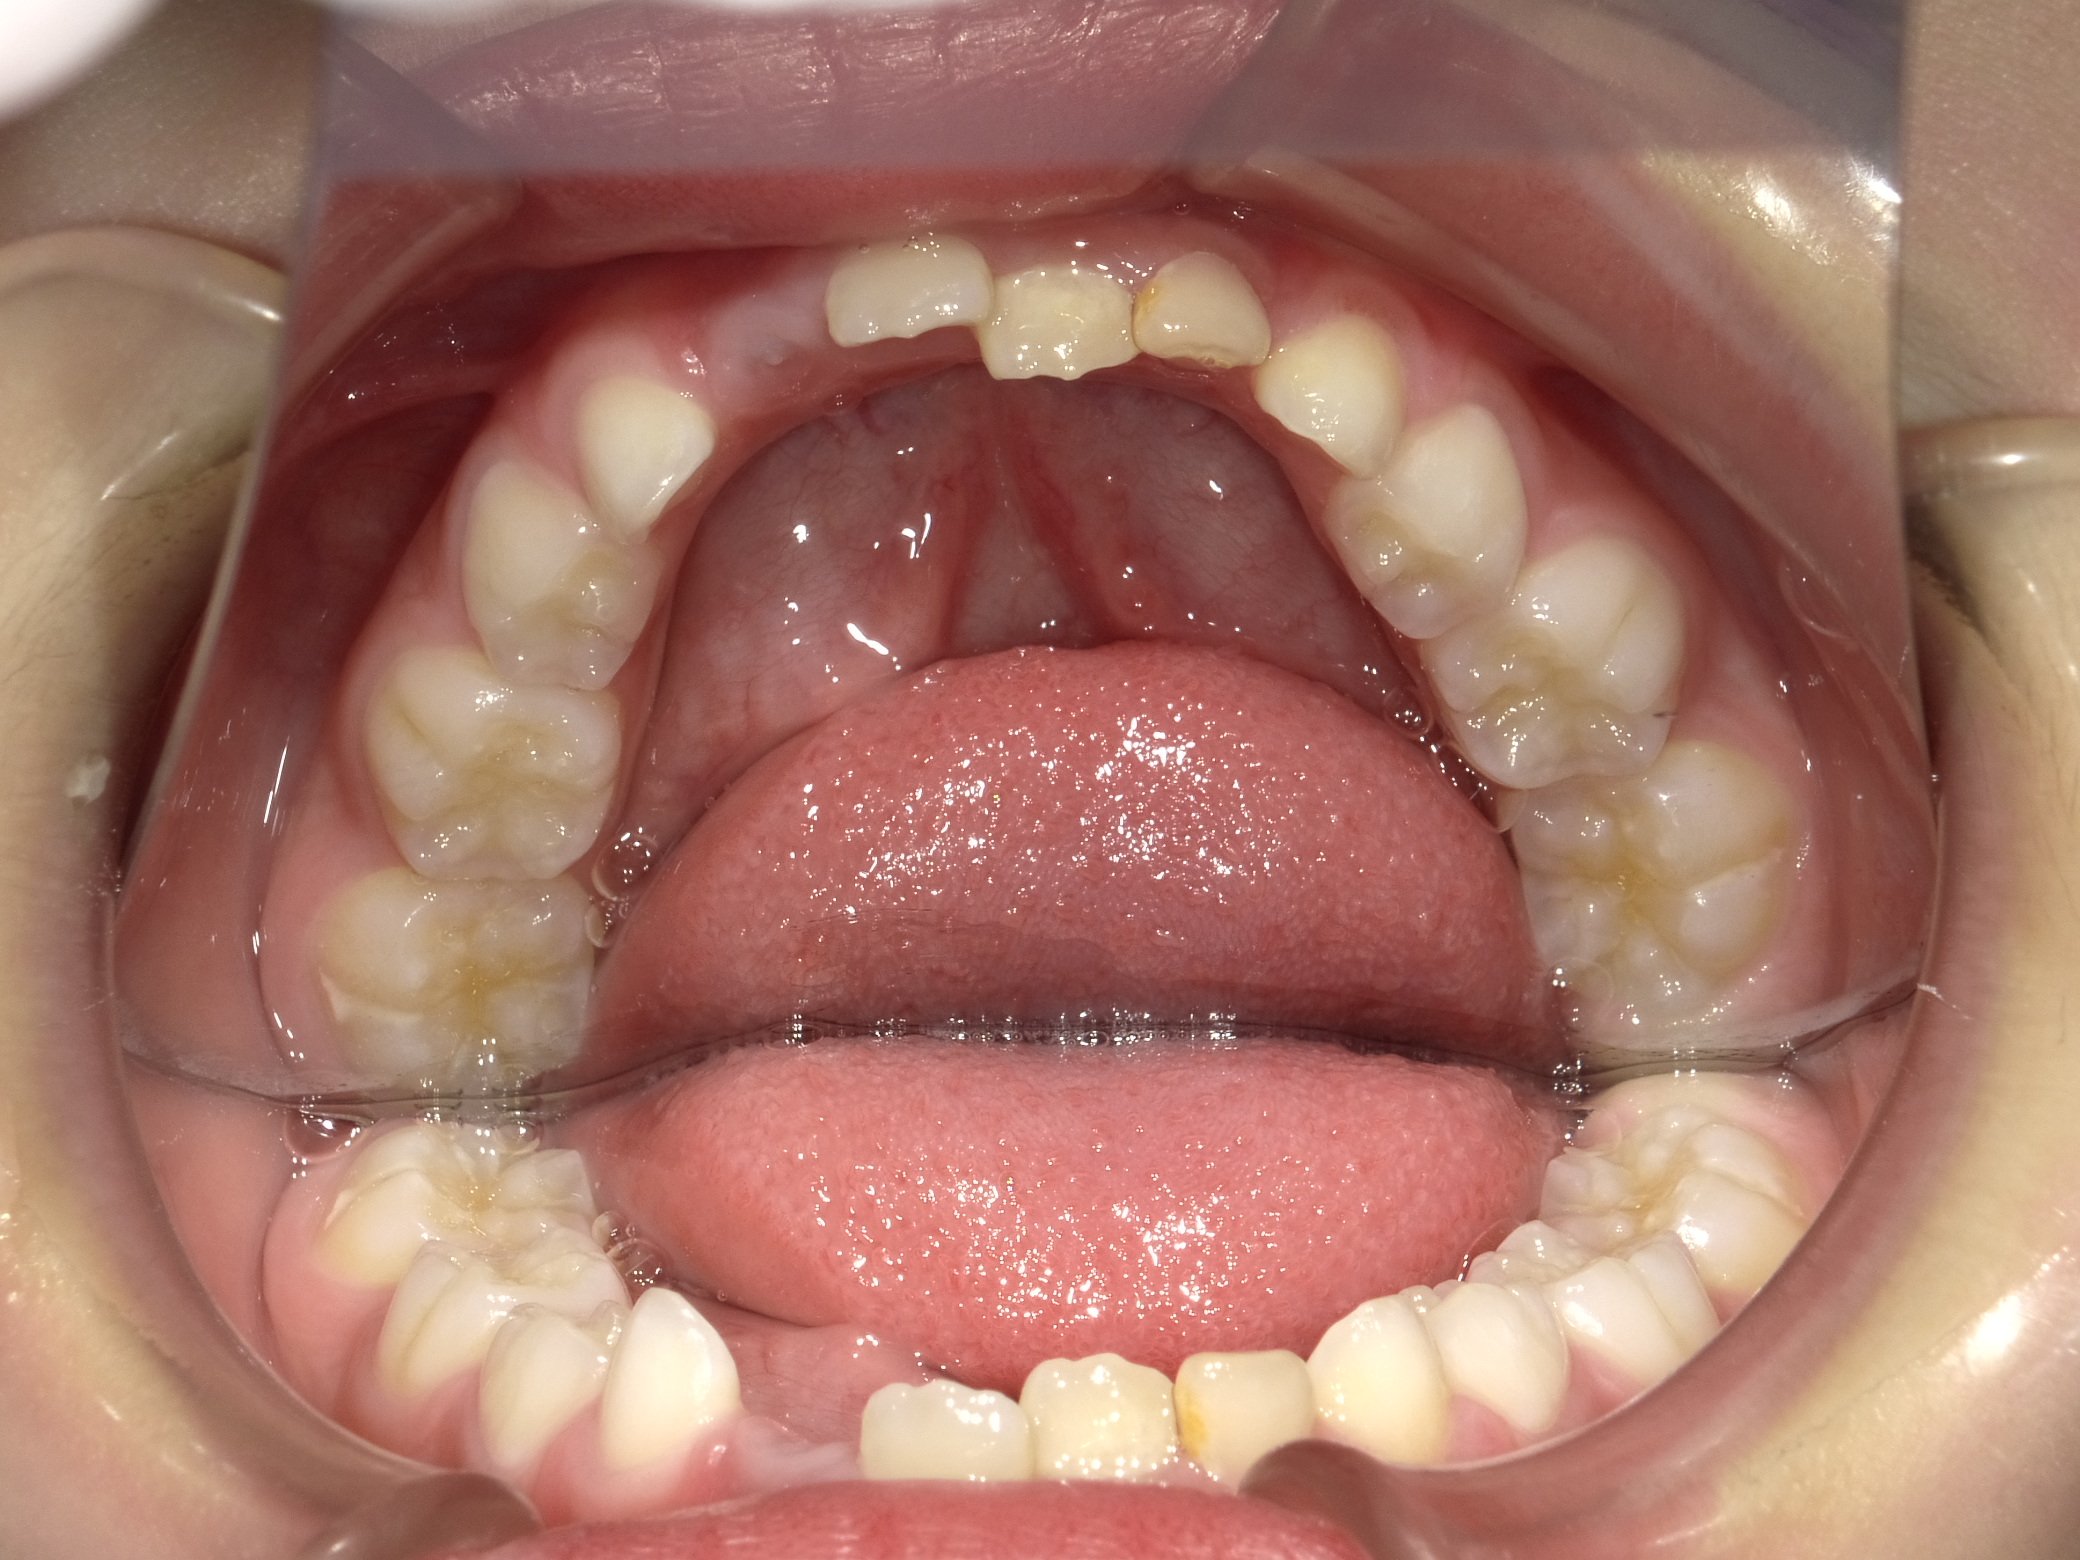

上顎